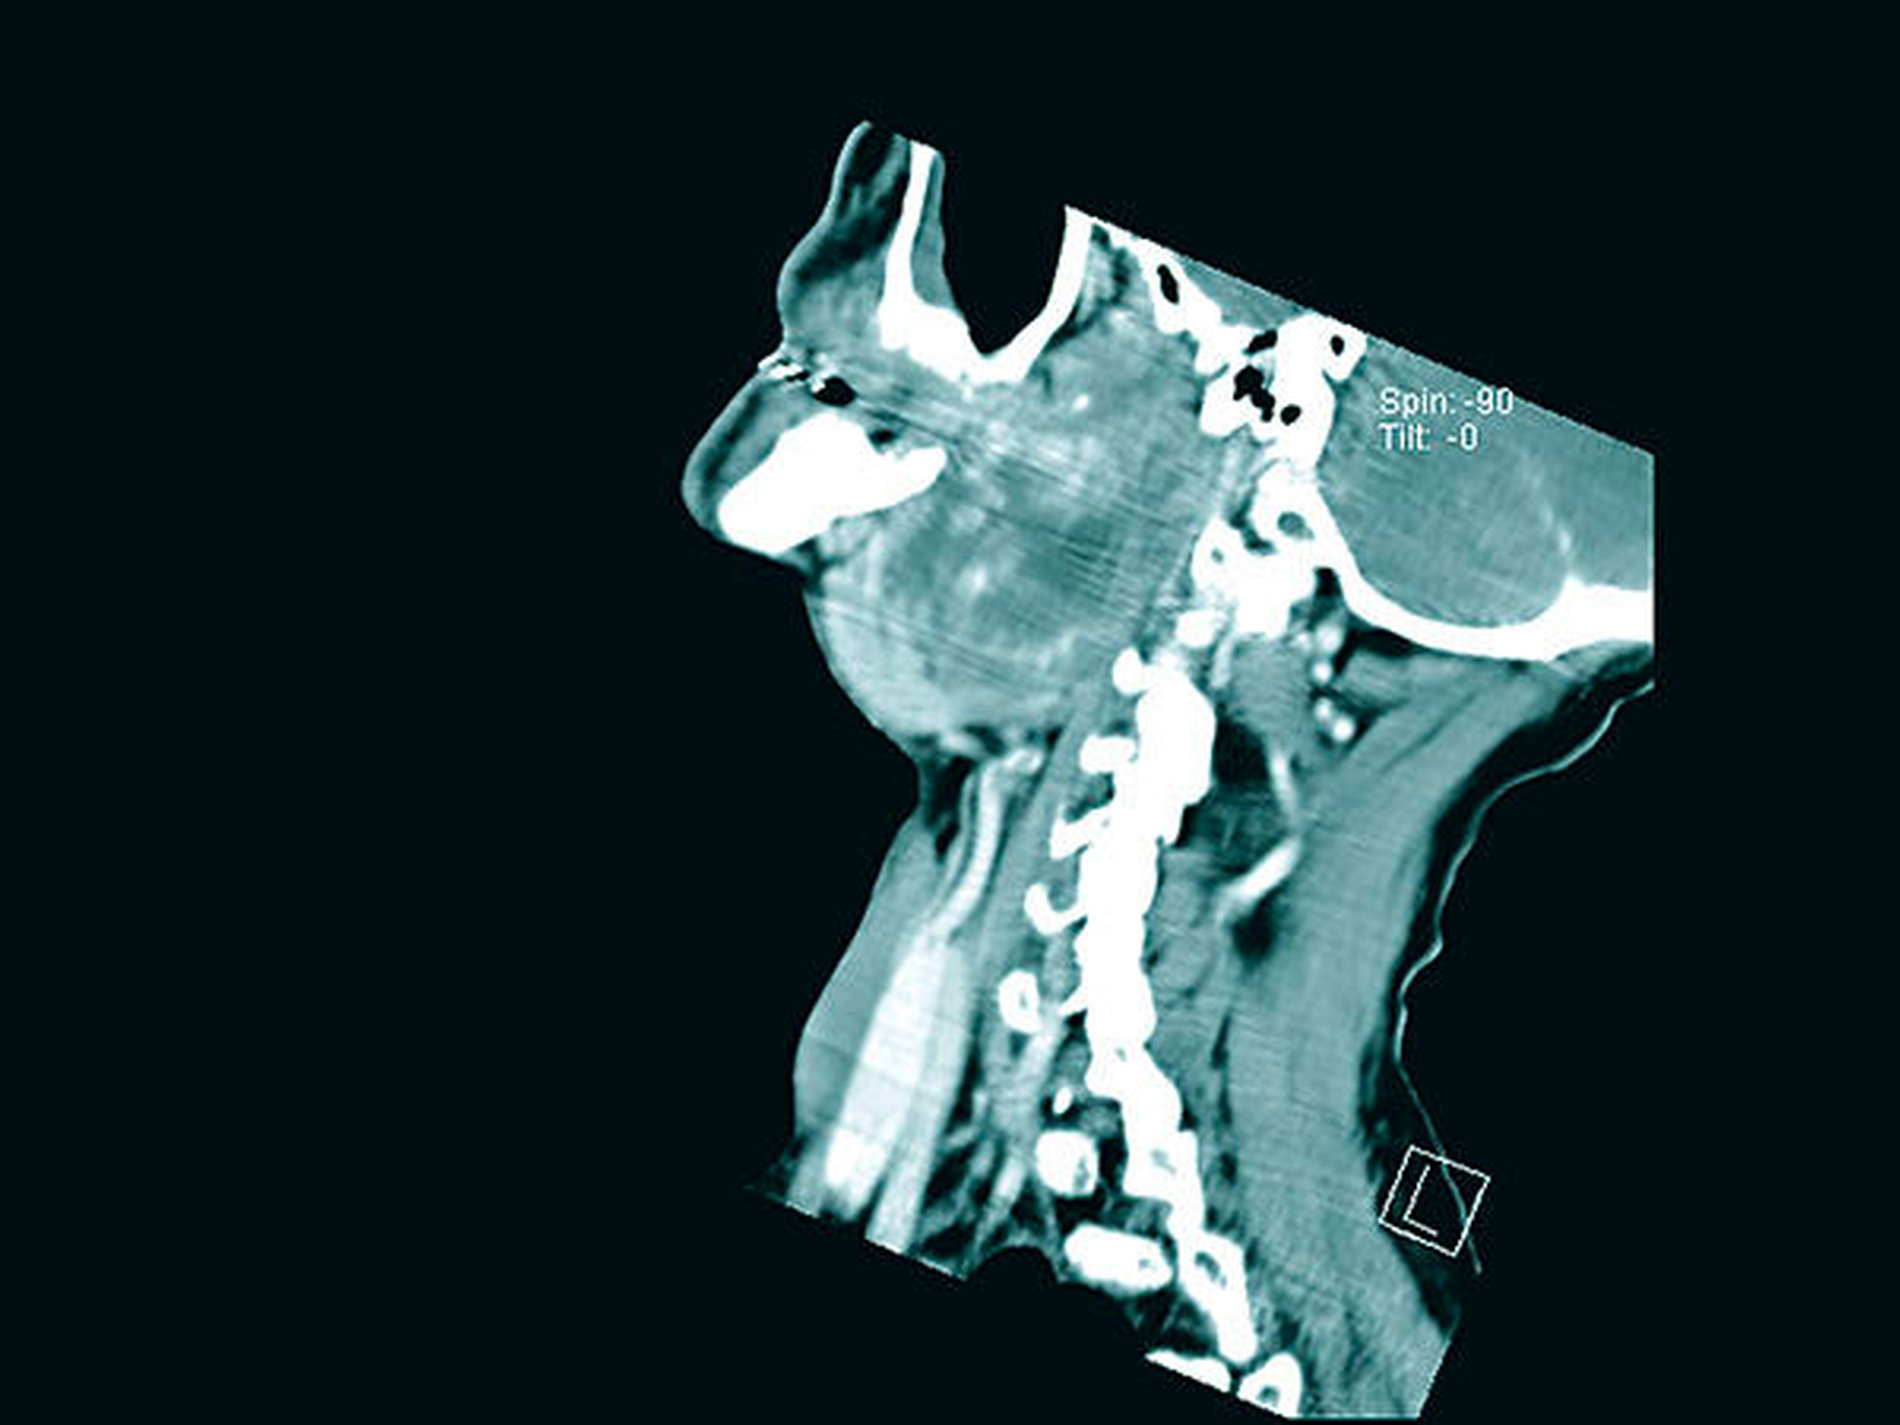

Im Rahmen einer ambulanten Probeentnahme von intra- und extraoral in Lokalanästhesie konnte nur Speicheldrüsengewebe im Sinne einer Sialadenitis mit Sialektasie gewonnen werden, so dass eine erneute Probenentnahme unter stationären Bedingungen von intraoral aus dem Parotistumor und aus dem Bereich der Leukoplakie im vorderen Mundboden erfolgte. Die Ausdehnung des Tumors ist auf den CT-Bildern deutlich zu erkennen (Abbildungen 1 bis 3).